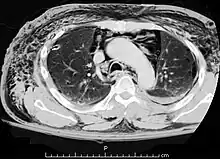

| A CT scan showing air in the mediastinum with subcutaneous emphysema, which can result in Hamman's syndrome | |

Hamman's syndrome, also known as Macklin's syndrome, is a syndrome of spontaneous subcutaneous emphysema[1] (air in the subcutaneous tissues of the skin) and pneumomediastinum (air in the mediastinum, the center of the chest cavity), sometimes associated with pain and, less commonly, dyspnea (difficulty breathing), dysphonia, and a low-grade fever.